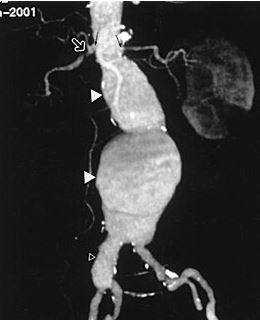

Аневризматические расширения брюшной аорты обозначены стрелками

Как выглядит аневризма аорты на КТ. Аневризма аорты - расширение основного артериального сосуда. Она может быть как в грудном отделе аорты, так и в брюшном, так и в обоих сразу. Сегодня при подозрении на аневризму аорты КТ выполняется обязательно. Исследование выявляет размеры и форму аневризмы, а также позволяет исключить опасное осложнение - расслоение стенки аорты!

![]()

Обследование брюшной аорты и ее ветвей с помощью КТ визуализирует поперечные размеры сосуда, вовлеченность стенки, локализацию возможных патологических изменений:

расслоение стенки сосуда;

ограниченное или генерализованное расширение поперечного диаметра аорты;

патологические изменения структуры сосудистой стенки;

нечеткость контуров аорты и ответвлений.